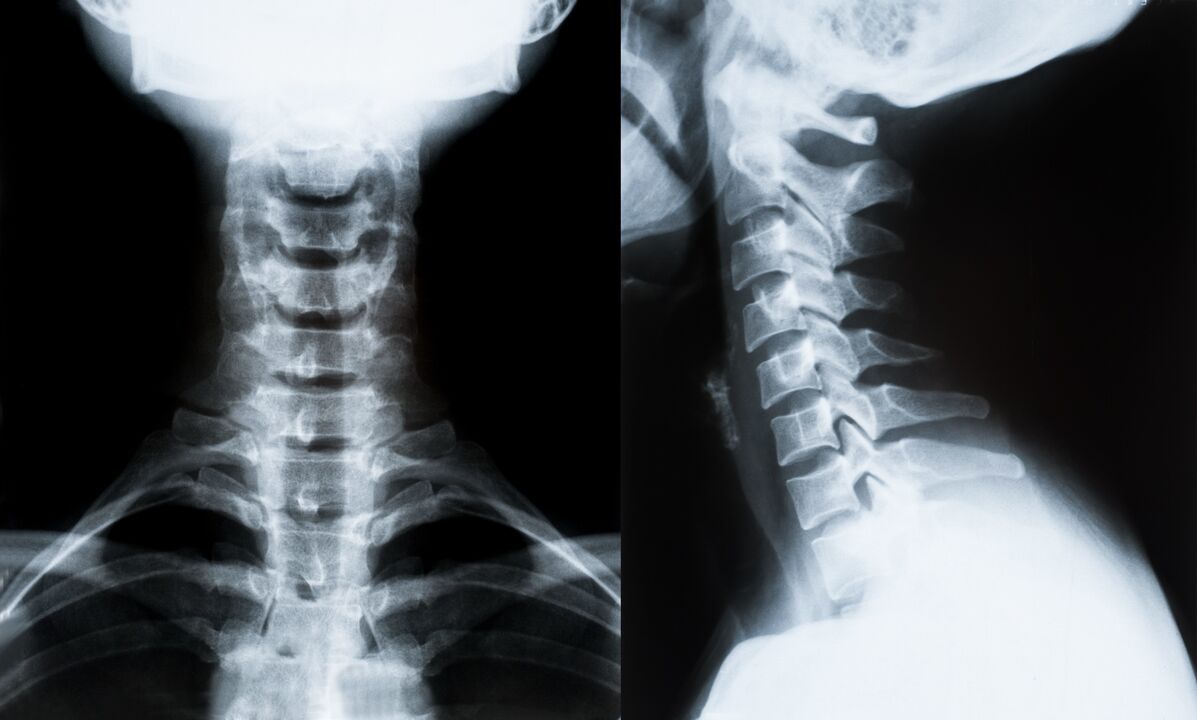

Główne metody diagnozy i dalszego określenia leczenia osteochondrozy kręgosłupa szyjnego:

- Rentgen. Najmniej skuteczna, ale tradycyjna metoda diagnostyczna.

- Rezonans magnetyczny jest najskuteczniejszą metodą diagnostyczną. Przy tego typu badaniu pacjenta widoczne są wszystkie niezbędne struktury.

- Jeżeli konieczne jest zmierzenie zmian, stosuje się tomografię komputerową. Określa obecność przepuklin i innych rzeczy.

- Ostatnią metodą jest ultradźwiękowe skanowanie dupleksowe. Ta metoda badawcza określa prędkość przepływu krwi w tętnicach.

Niemożliwe jest dokładne określenie choroby kręgosłupa w domu.